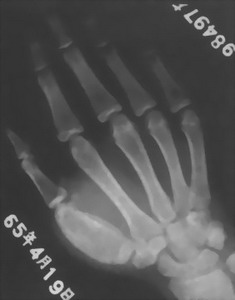

指骨結核掌骨結核共稱短骨的骨幹結核,發病率占上肢骨與關節結核的次位,僅低於肘關節結核,占全身骨與關節結核的4.88%。患者以兒童居多,成人發病少見。掌、指骨結核繫結核菌經血源途徑引起發病。骨幹結核的病理變化以增生為主,溶骨性破壞次之,死骨形成比較少見。手部短骨骨幹結核也以增生為主,死骨形成有時可見到,其病理變化與長骨骨幹略有不同。常見有氣臌的改變,即骨質膨脹、變薄,髓腔因溶骨性破壞而擴大。死骨形成比長骨骨幹結核為多。可能因骨體細小,病變容易波及關節的機會比長骨骨幹結核要多。手足短管狀骨結核的發病率比長骨骨幹高得多,考慮是因為短管狀骨周圍肌肉較小或缺如,缺乏肌肉的保護作用。另外短管狀骨的營養血管較細,血流速度緩慢,細菌栓子容易在局部停留而發病的緣故。在手部掌指骨結核中,掌骨的病例數高於指骨末節指骨很少見。在5個手指中,12、3指所屬的掌骨和指骨的患病率較高4、5指所屬的掌、指骨患病率較低。